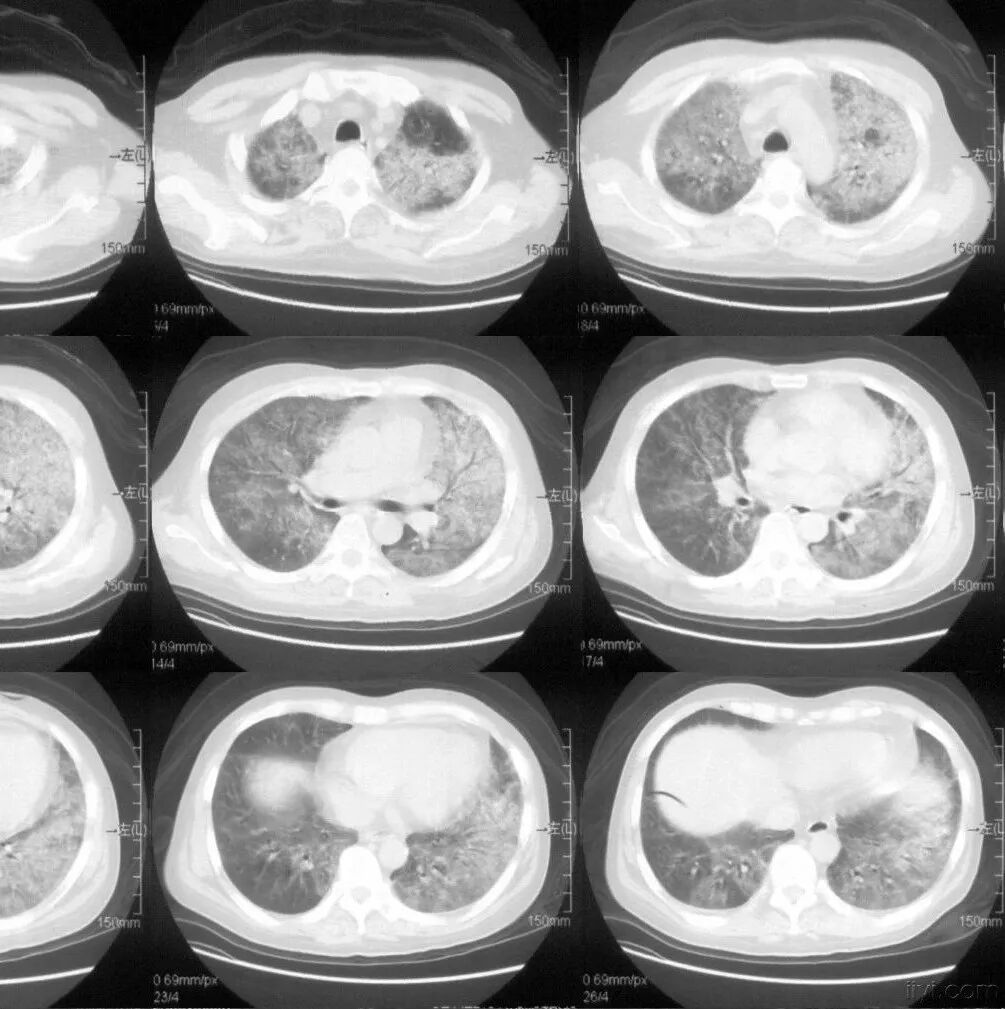

CT即电子计算机断层扫描,它是利用精确准直的X线束、γ射线、超声波等,与灵敏度极高的探测器一同围绕人体的某一部位作一个接一个的断面扫描,供完整的三维信息,具有扫描时间快,图像清晰等特点,可用于多种疾病的检查。

CT的辐射剂量相较于X光片大一点,普通健康体检检查尽量选择低剂量CT筛查而不是常规CT,怀孕妇女不宜进行CT检查。

肺部CT 检查

CT检查目前有两种检查方式

1、普通平扫

即常规的CT检查,一般只需要躺在CT机上面进行扫描便可,无需打造影剂,速度快,方便简洁,故常作为初次检查、急性病变的首要检查方案。

2、增强扫描

在平扫CT的基础上,静脉注射造影剂(常用碘对比剂),通过血液循环跑到全身组织器官中,相当于给平扫的CT润色一番,有助于更加准确地分辨血液循环丰富的器官组织病变,如肿瘤。

一般来说,如果普通平扫CT能看清楚病变,并能做出明确的影像学诊断,那就不需要进一步做增强CT了,否则,需要完善增强CT以明确诊断。

极少部分人会对造影剂有不良反应,故检查时需要医护人员及家属或朋友陪同。

CT检查的作用

胸部 肺、胸膜及纵膈各种肿瘤、肺结核、肺炎、支气管扩张、肺脓肿、囊肿、肺不张、气胸、骨折等;对于显示肺部病变有非常满意的效果,对肺部创伤、感染性病变、肿瘤等均匀有很高的诊断价值。对于纵隔内的肿物、淋巴结以及胸膜病变等的显示非常清晰也令人满意,可以显示肺内团块与纵隔关系等。